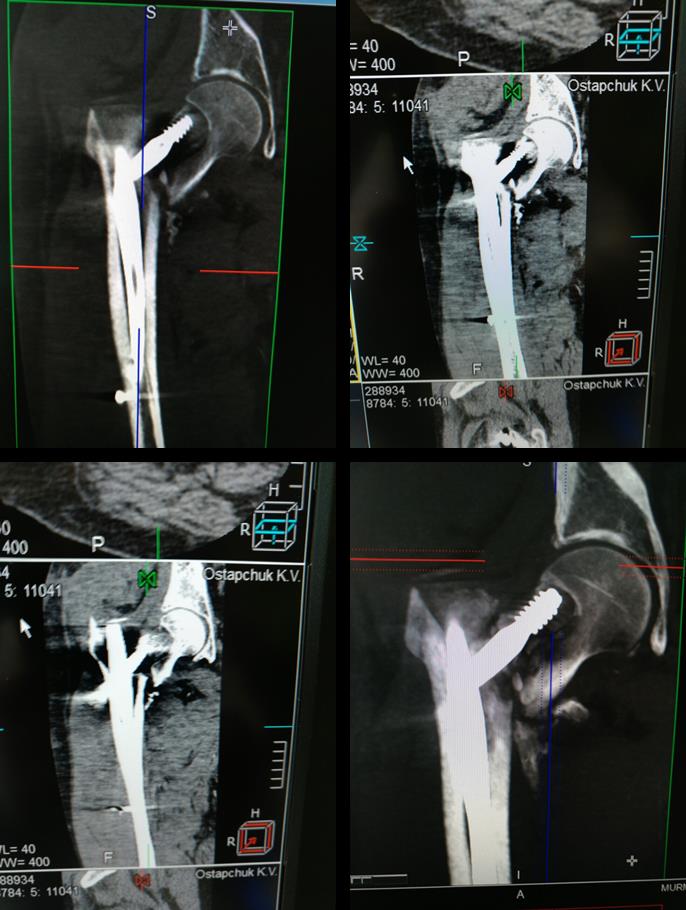

[Ortho] Выполнен остеосинтез Gamma3 1,5 мес назад

провели предоперационную компьютерную томографию